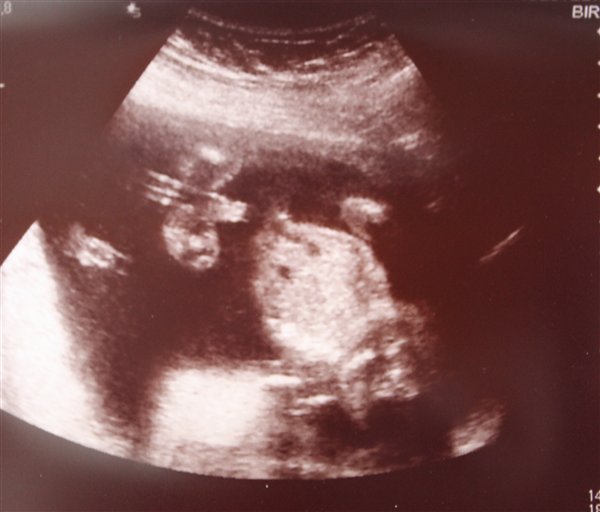

Jeg kender et par stykker fra MAndens familie, de har fået et forkert svar ang. kønnet..

Vi har fået at vide at, vi venter endnu en smuk lille prinsesse pige her lige om lidt og de sagde os at de var ikk sikre på noget, så håber de har ret i at det er en pige, får jeg snart at se